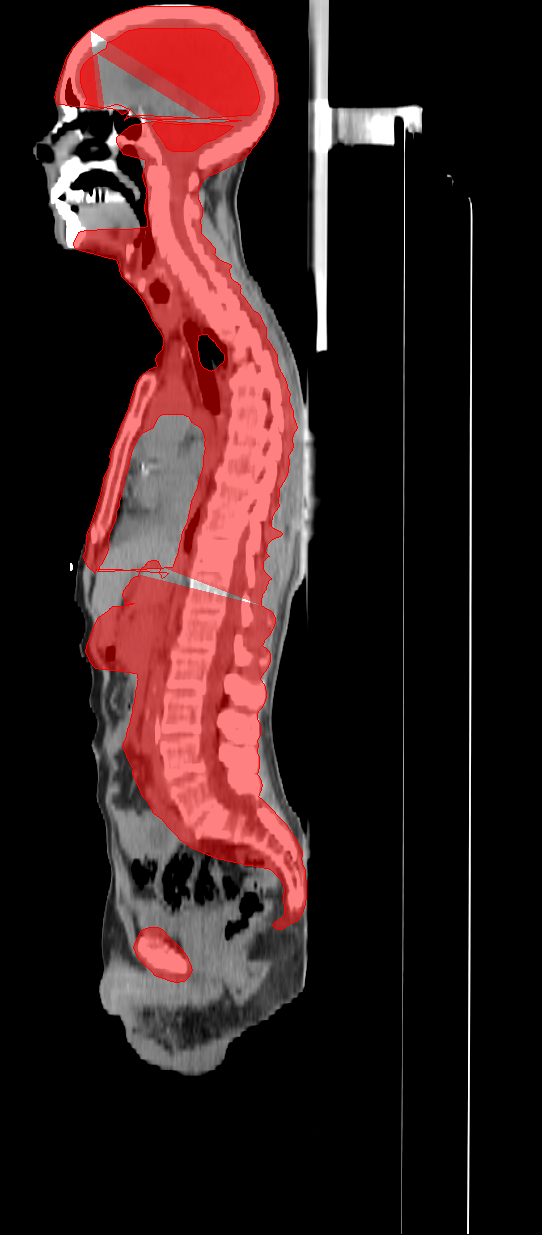

The TMLI clinical target volume (CTV) encompassed the bone marrow (CTV_BM), spleen (CTV_Spleen), and all lymph node chains (CTV_LN). The CTV_BM was considered equivalent to the skeletal bones, with the chest wall added to the ribs to account for breathing motions. To minimize oral cavity toxicity, the mandible was excluded from the CTV_BM, along with the hands, which have an extremely limited bone marrow presence. The total planning target volume (PTV_Tot) was defined as the union of three PTVs, derived from the isotropic expansion of three corresponding CTVs, as follows: (i) PTV_BM = CTV_BM + 2 mm (+8 mm for arms and legs) to account for setup margin; (ii) PTV_Spleen = CTV_Spleen + 5 mm to account for breathing motions and setup margin; and (iii) PTV_LN = CTV_LN + 5 mm to account for target residual motion and setup margin.

Figure 1 presents an example of the PTV_Tot defined for a patient. The dataset contains the CT scans of each patient and the corresponding PTV_Tot structure stored using the DICOM-RT format. In this study, we trained a model to directly segment the PTV_Tot target. Unlike other PTVs and CTVs, the PTV_Tot is the only target consistently annotated by ROs for all 100 patients included in the dataset.